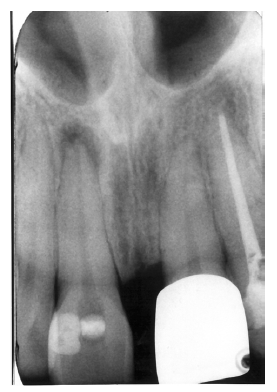

Figure 2 - Advanced Enamel Caries

Figure 2

Figure 2 illustrates advanced enamel caries on the mesial surface of the premolar.